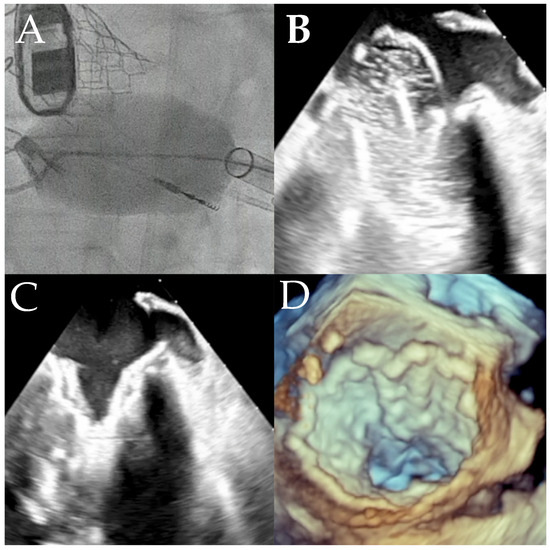

Objectives: This study aims to review short- to intermediate-term outcomes after transapical transcatheter mitral valve replacement (TMVR) using the Tendyne valve system in patients with mitral annular calcification (MAC), including off-label use in severe MAC. Methods: This retrospective sub-analysis of the multicenter Tendyne European Experience (TENDER) registry included fifty-three MAC patients who underwent commercial Tendyne-TMVR in 15 European heart centers between 01/2020 and 06/2022. Patients were assigned to the mild (n = 16), moderate (n = 17), and severe MAC (n = 20) cohorts according to Guerrero’s MAC score. Additionally, the predictive value of detailed computed tomography-derived, quantitative, and qualitative MAC characteristics on clinical outcome was tested. Results: In this overall multimorbid patient population, predominantly treated for severe mitral regurgitation (MR), technical success rates were comparable among cohorts (mild MAC: 93.8% vs. moderate MAC: 88.2%vs. severe MAC: 95%, p = 0.720). Complete MR abolishment was achieved in 88.7% of patients, with no significant difference between cohorts in the incidence of residual MR >1+ (n = 1 in moderate MAC; p = 0.350) or paravalvular leakage >1+ (PVL; n = 2 in moderate MAC, p = 0.118) at discharge. All three in-hospital deaths occurred in patients with moderate MAC (p = 0.034). There were no significant differences in 1-year cardiovascular mortality (mild MAC: 23.1% vs. moderate MAC: 6.3% vs. severe MAC: 0%, p = 0.085) and overall mortality (mild MAC: 38.5% vs. moderate MAC: 43.8% vs. severe MAC: 18.8%, p = 0.291) between the cohorts, including in patients with off-label severe MAC. The rate of heart failure hospitalization at 1 year was significantly higher in the moderate MAC cohort (mild MAC: 10% vs. moderate MAC: 61.5%, severe MAC: 21.4%, p = 0.017). Further quantitative and qualitative MAC parameters showed no significant impact on 1-year survival or hemodynamic prosthetic performance. Conclusions: This MAC-focused analysis suggests that Valve-in-MAC using the Tendyne valve system is safe, technically feasible, and associated with satisfying hemodynamic and clinical outcomes, irrespective of MAC morphology. Full article

Graphical abstract